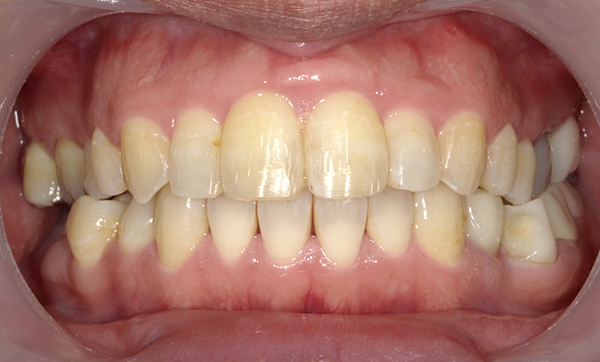

症例_013 前歯「八の字/V字型」症例

治療期間:8ヶ月金額:30万円+税20代女性八の字/V字型捻転歯上の前歯だけ